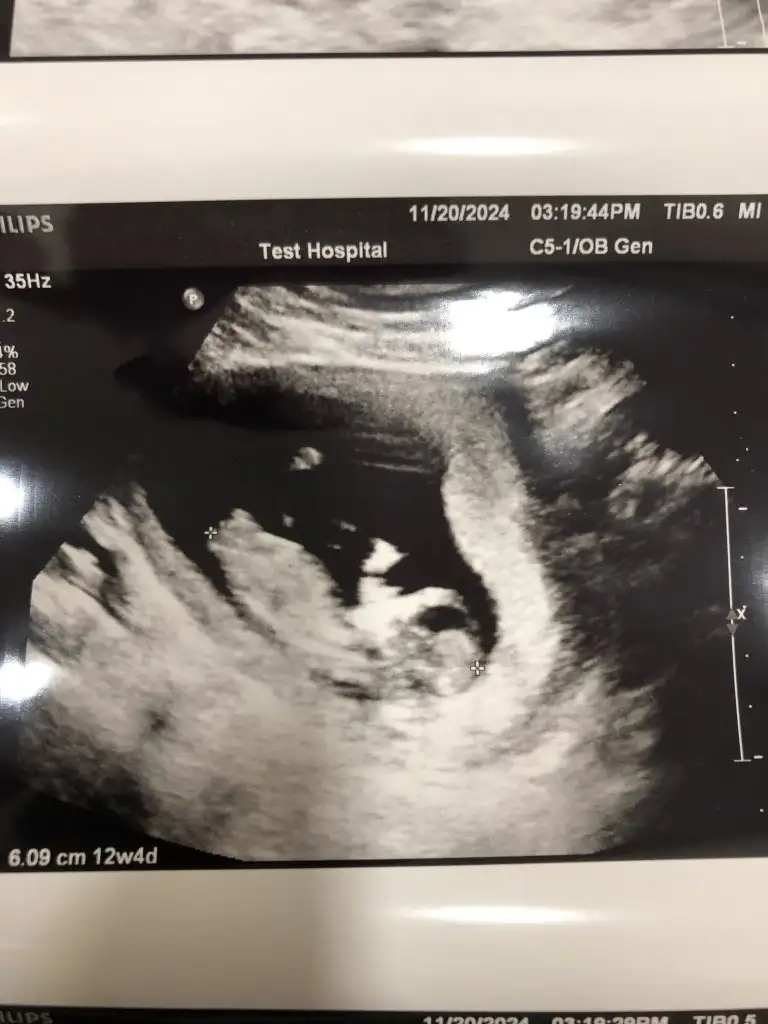

Bana da bakar mısınız sanki çıkıntı yukarı çıkıyor gibi erkeğe benzettim ama düz de değil tam. Daha erken mi acaba kafa yapısı erkek gibi

• IMG_5349.webp

IMG_5349.webp

48,4 KB · Görüntüleme: 52

• IMG_5348.webp

IMG_5348.webp

30 KB · Görüntüleme: 46

• IMG_5347.webp

IMG_5347.webp

30,3 KB · Görüntüleme: 51